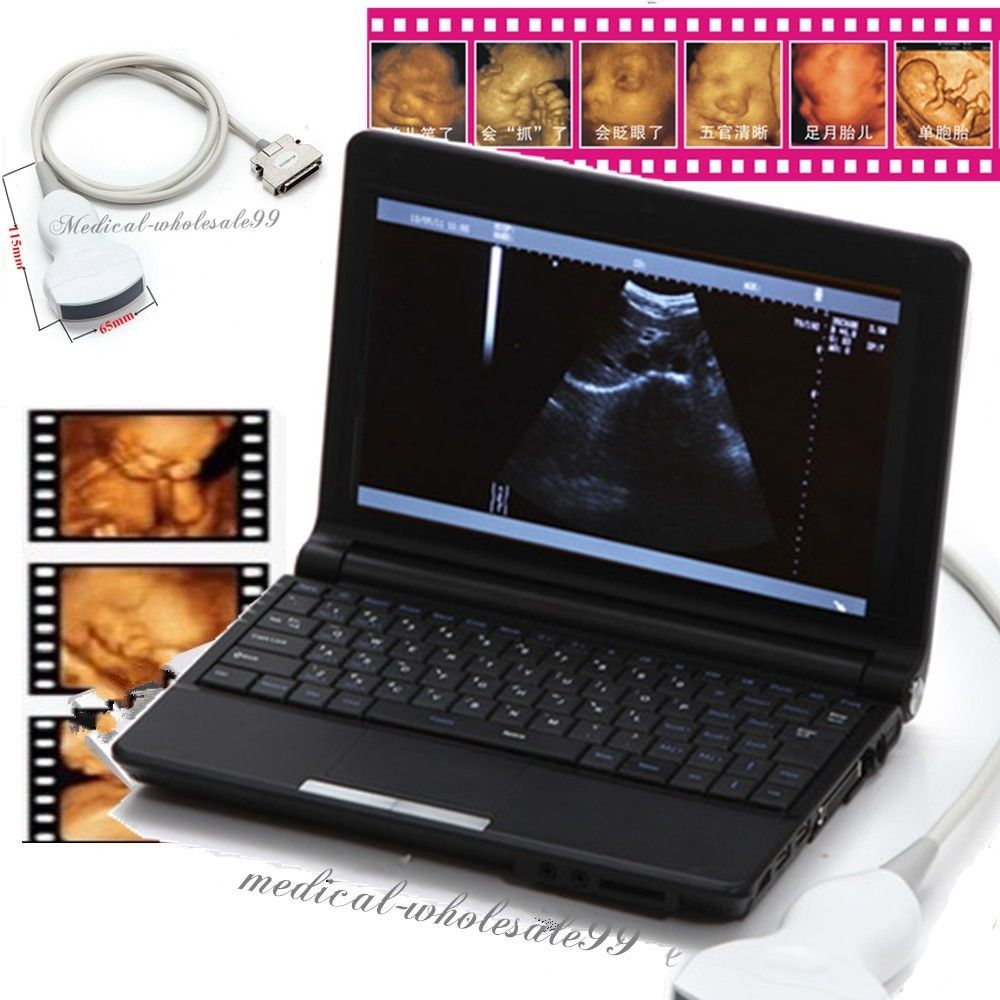

Model: RUS-9000F

Optional: 3.5MHz R60 convex probe

7.5MHz linear probe: 6.5MHz Trans-vaginal probe

Display /Monitor / Screen: 10.1-inch high-resolution TFT LCD

5.0MHz Micro-convex probe: Video Printer Sony UP-897

Probe frequency: Probe frequency

Brand: Carejoy